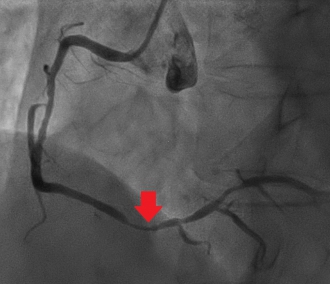

その後撮影した冠動脈造影。CTと同様、右冠動脈に高度狭窄を認める(矢印)。